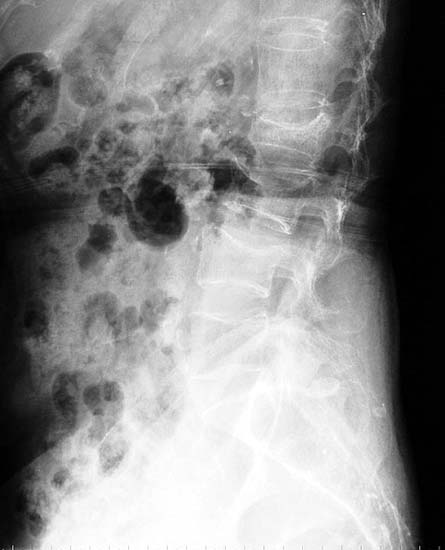

75岁女性,腰椎2、3压缩骨折2个月,疼痛明显

将骨水泥注射到骨折塌陷的两个椎体,迅速止痛,当天下地活动